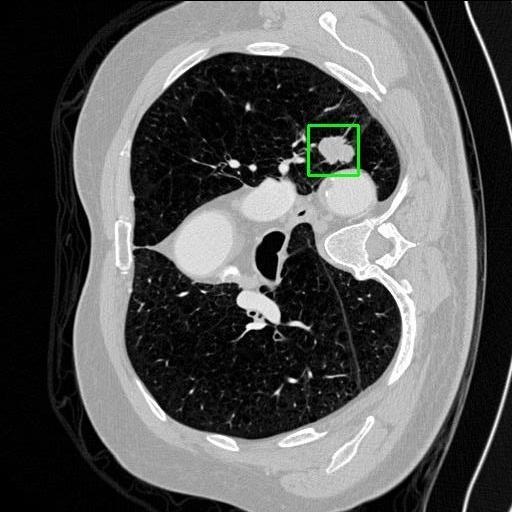

We developed an AI-based system using deep learning models for analyzing lung CT scans to detect and classify pulmonary nodules. We chose the YOLOv11 architecture for its enhanced object detection capability and adapted it specifically for medical imaging, incorporating pixel-level precision and severity classification.

Classification into three severity levels with colored bounding boxes.

Successfully built and deployed an AI model (YOLOv11) capable of detecting lung nodules in CT scans with high accuracy and real-time performance.

Designed a severity classification system that categorizes nodules into null, moderate, and severe using colored bounding boxes, assisting in rapid clinical decision-making.